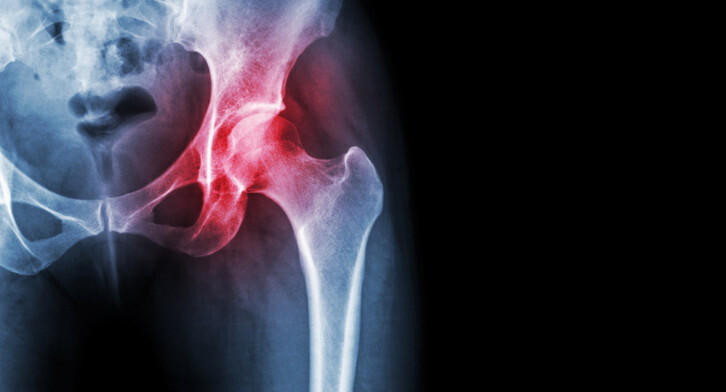

Osteoarthritis not only causes pain, but also makes it difficult to do a variety of everyday things. When your joints are stiff and achy, climbing stairs, buttoning your shirt, or getting in and out of the bathtub without falling become more challenging than you could ever have imagined. Adding chiropractic care to your osteoarthritis treatment plan can reduce both pain and stiffness.

- Keep Pain Under Control. Osteoarthritis happens when the cartilage at the ends of the bones in a joint wears away. Without that protective cushioning, the bones grind together every time you move the joint, causing jolts of pain. Chiropractic adjustments realign your joints and reduce painful pressure on the bones and cartilage. Self-reported pain levels in patients who had osteoarthritis of the neck decreased from 8.6 to 2.6 after receiving manipulation (adjustments) and mechanical mobilization device therapy, according to a research study published in the Journal of Manipulative and Physiological Therapeutics.

- Decrease Inflammation. Joint inflammation, a key factor in both pain and stiffness, is more likely to occur when your joints are misaligned. When misalignments are corrected, inflammation improves.